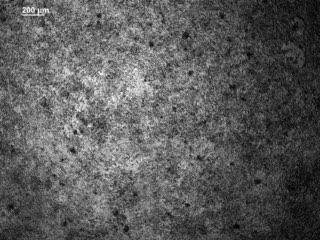

This shows a group of embryonic stem cells currently being transformed into beating heart muscle cells, or cardiomyocytes in a petri dish.

(Photo Credit: Jeff Alexander)